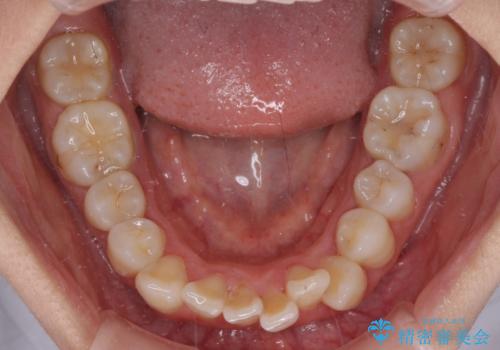

- 上下前歯のデコボコを改善したいとのことで来院された患者様です。

マウスピースを長時間装着し続ける自信はあまりないとのことでしたが、目立たない装置であれば頑張って装着するとのことで、インビザラインによる矯正治療を行うこととしました。

初めの1年くらいは何とか頑張って装着してくださいましたが、途中から変化をあまり感じられなくなり、日々の装着時間は徐々に短くなってしまいました。

前歯のデコボコはもっと改善できましたが、3年半が経過し、初診時と比べたら大幅に良くなったとのことで終了することとなりました。